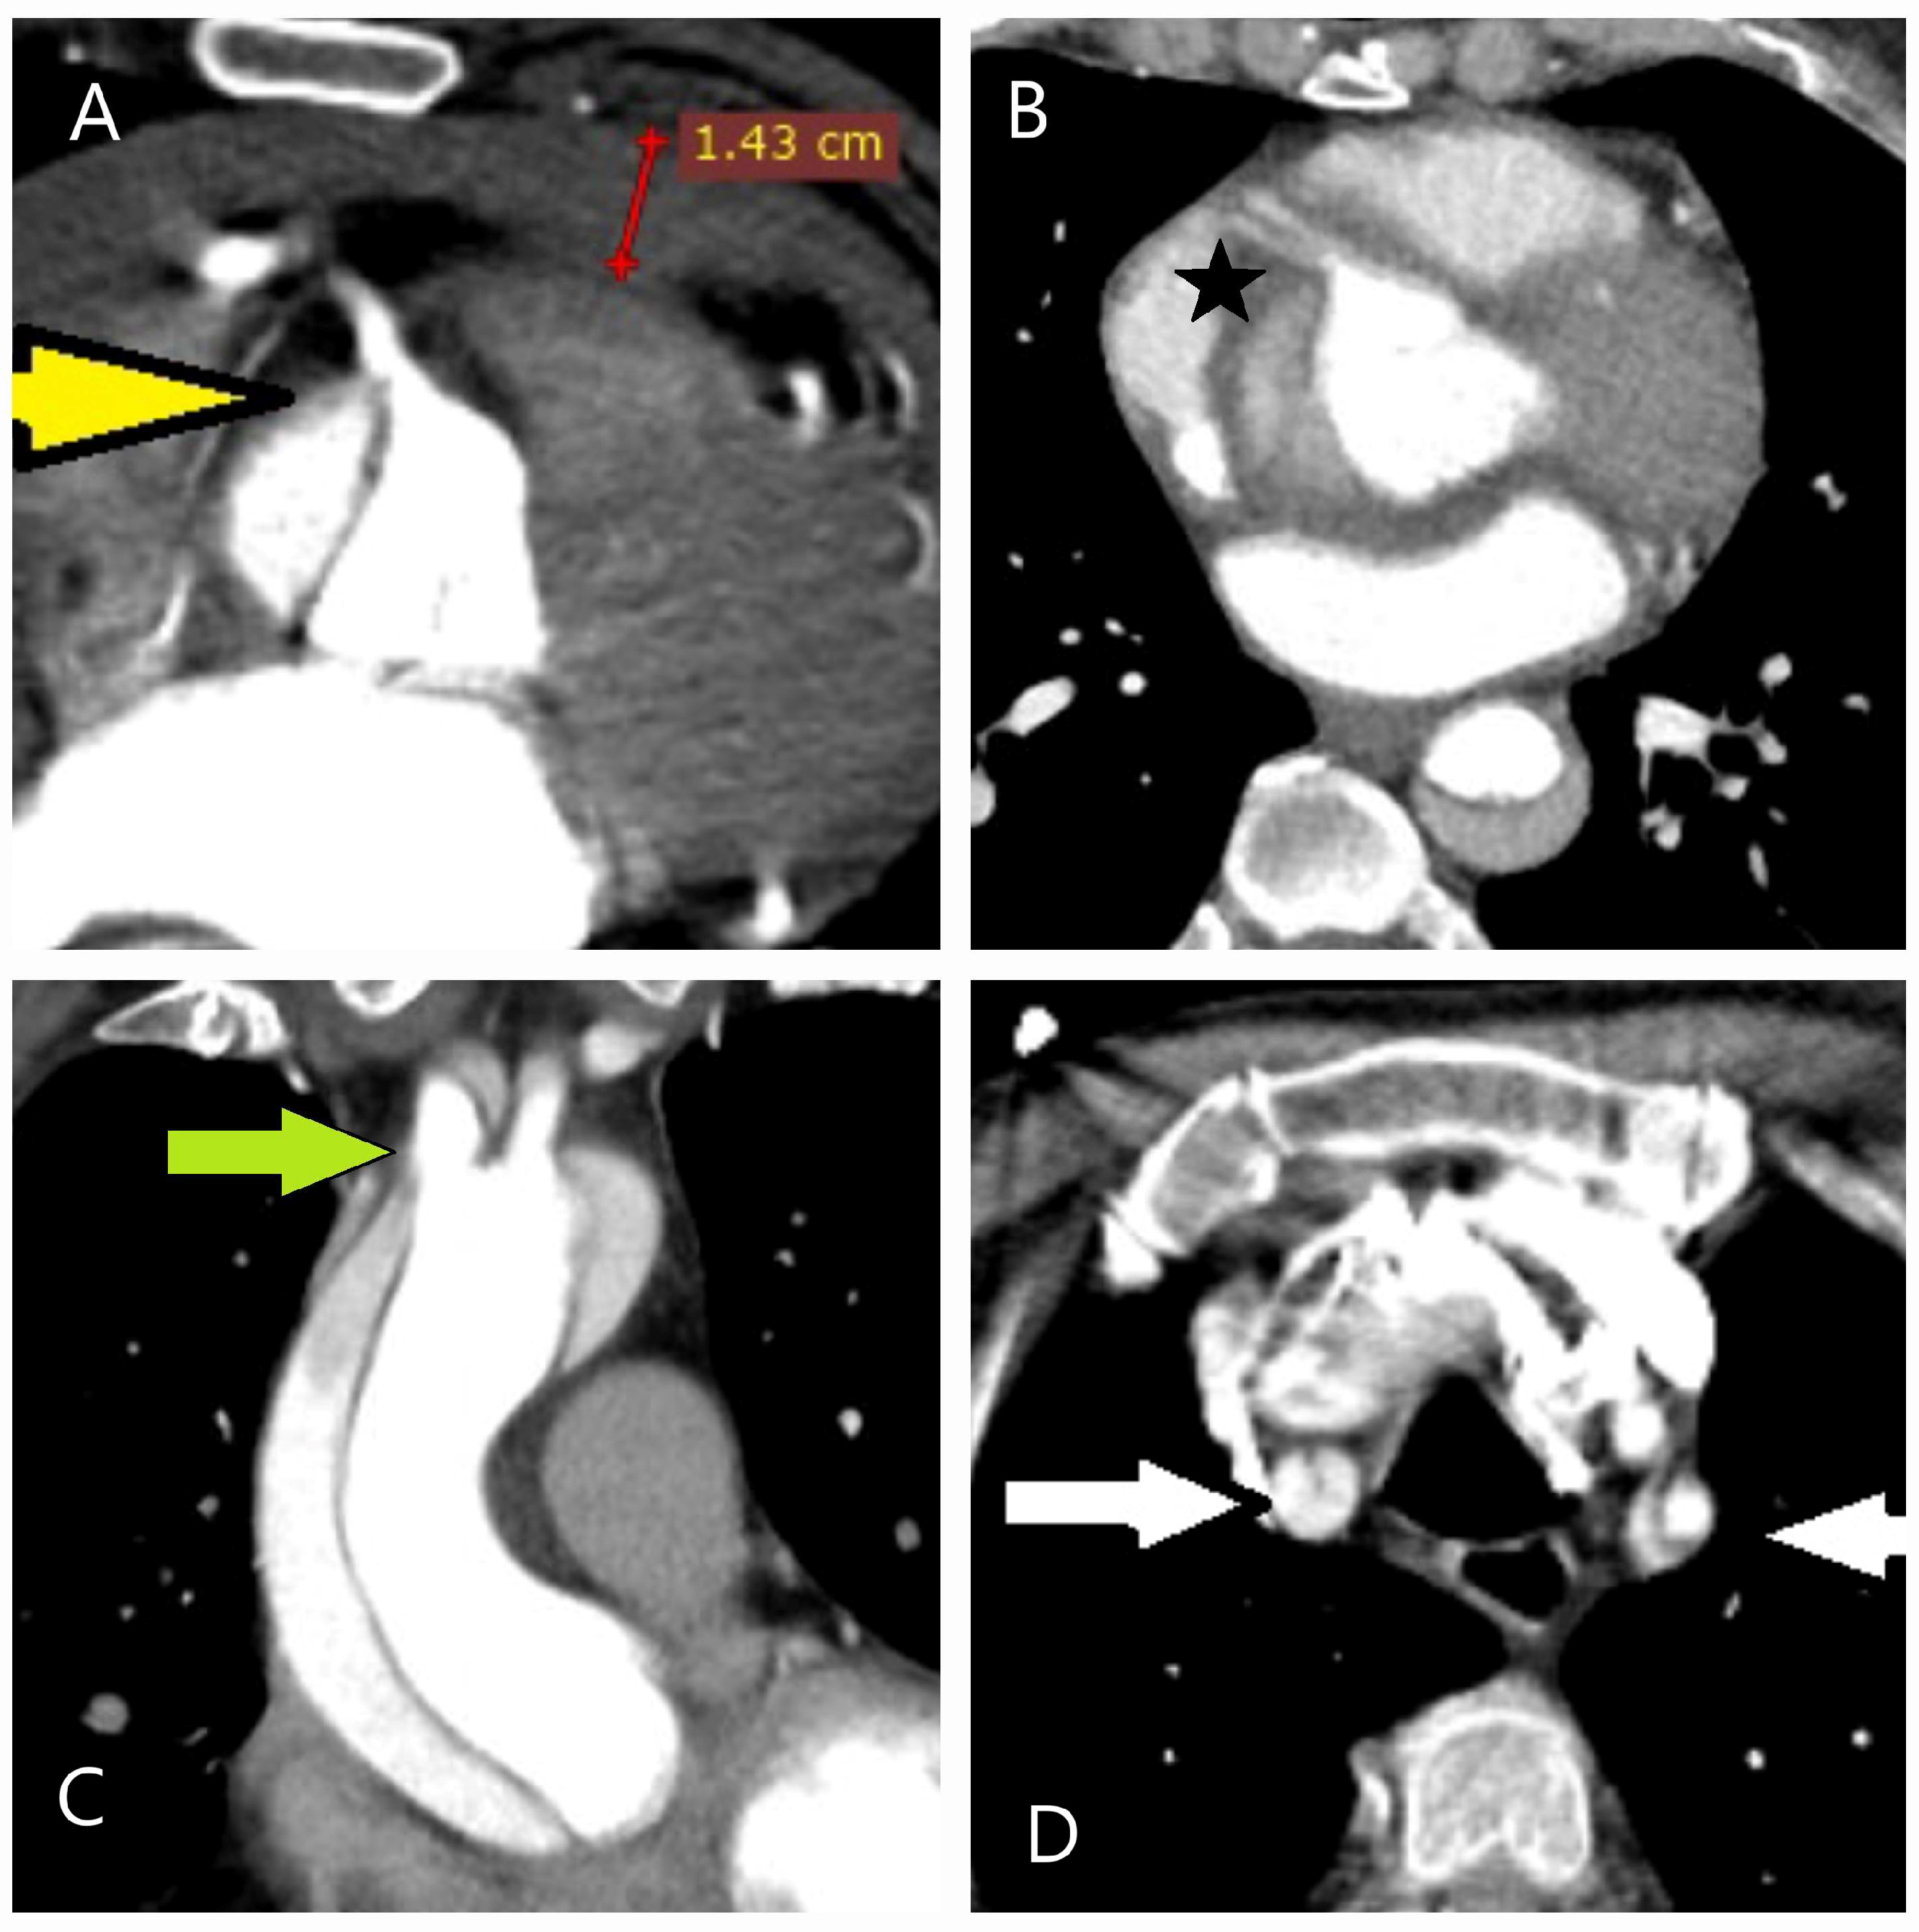

5.2.3. Computed Tomography